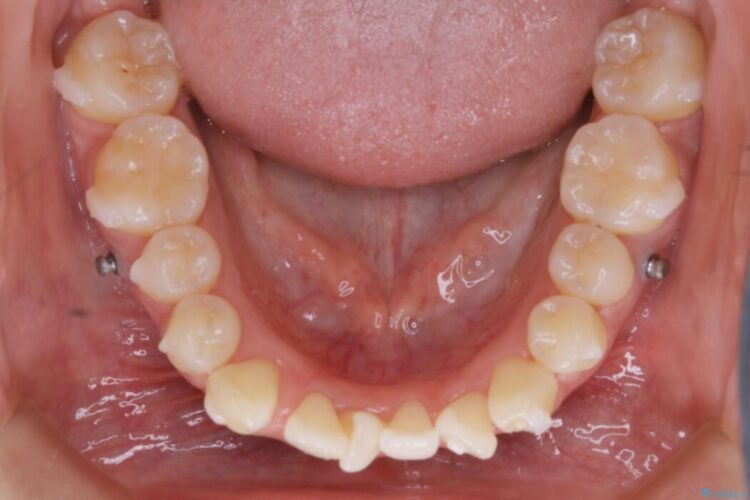

本症例では奥歯から順に移動させるため前歯の変化を感じるには時間が掛かりましたが、インビザライン装置とマイクロインプラントを併用することで健康な歯を抜歯することなく歯列をきれいに整えることができました。

マイクロインプラントとは矯正治療で使用する小さなネジのことです。

このネジを支点とし歯を引っ張ることで効率的に動かすことで、治療期間の短縮や従来の矯正治療では難しかった動きも対応が可能になります。

埋入することによる痛みはほとんどありませんが、数日ほど違和感を感じる方はおられます。また治療が終了次第、簡単に取り外すことができます。